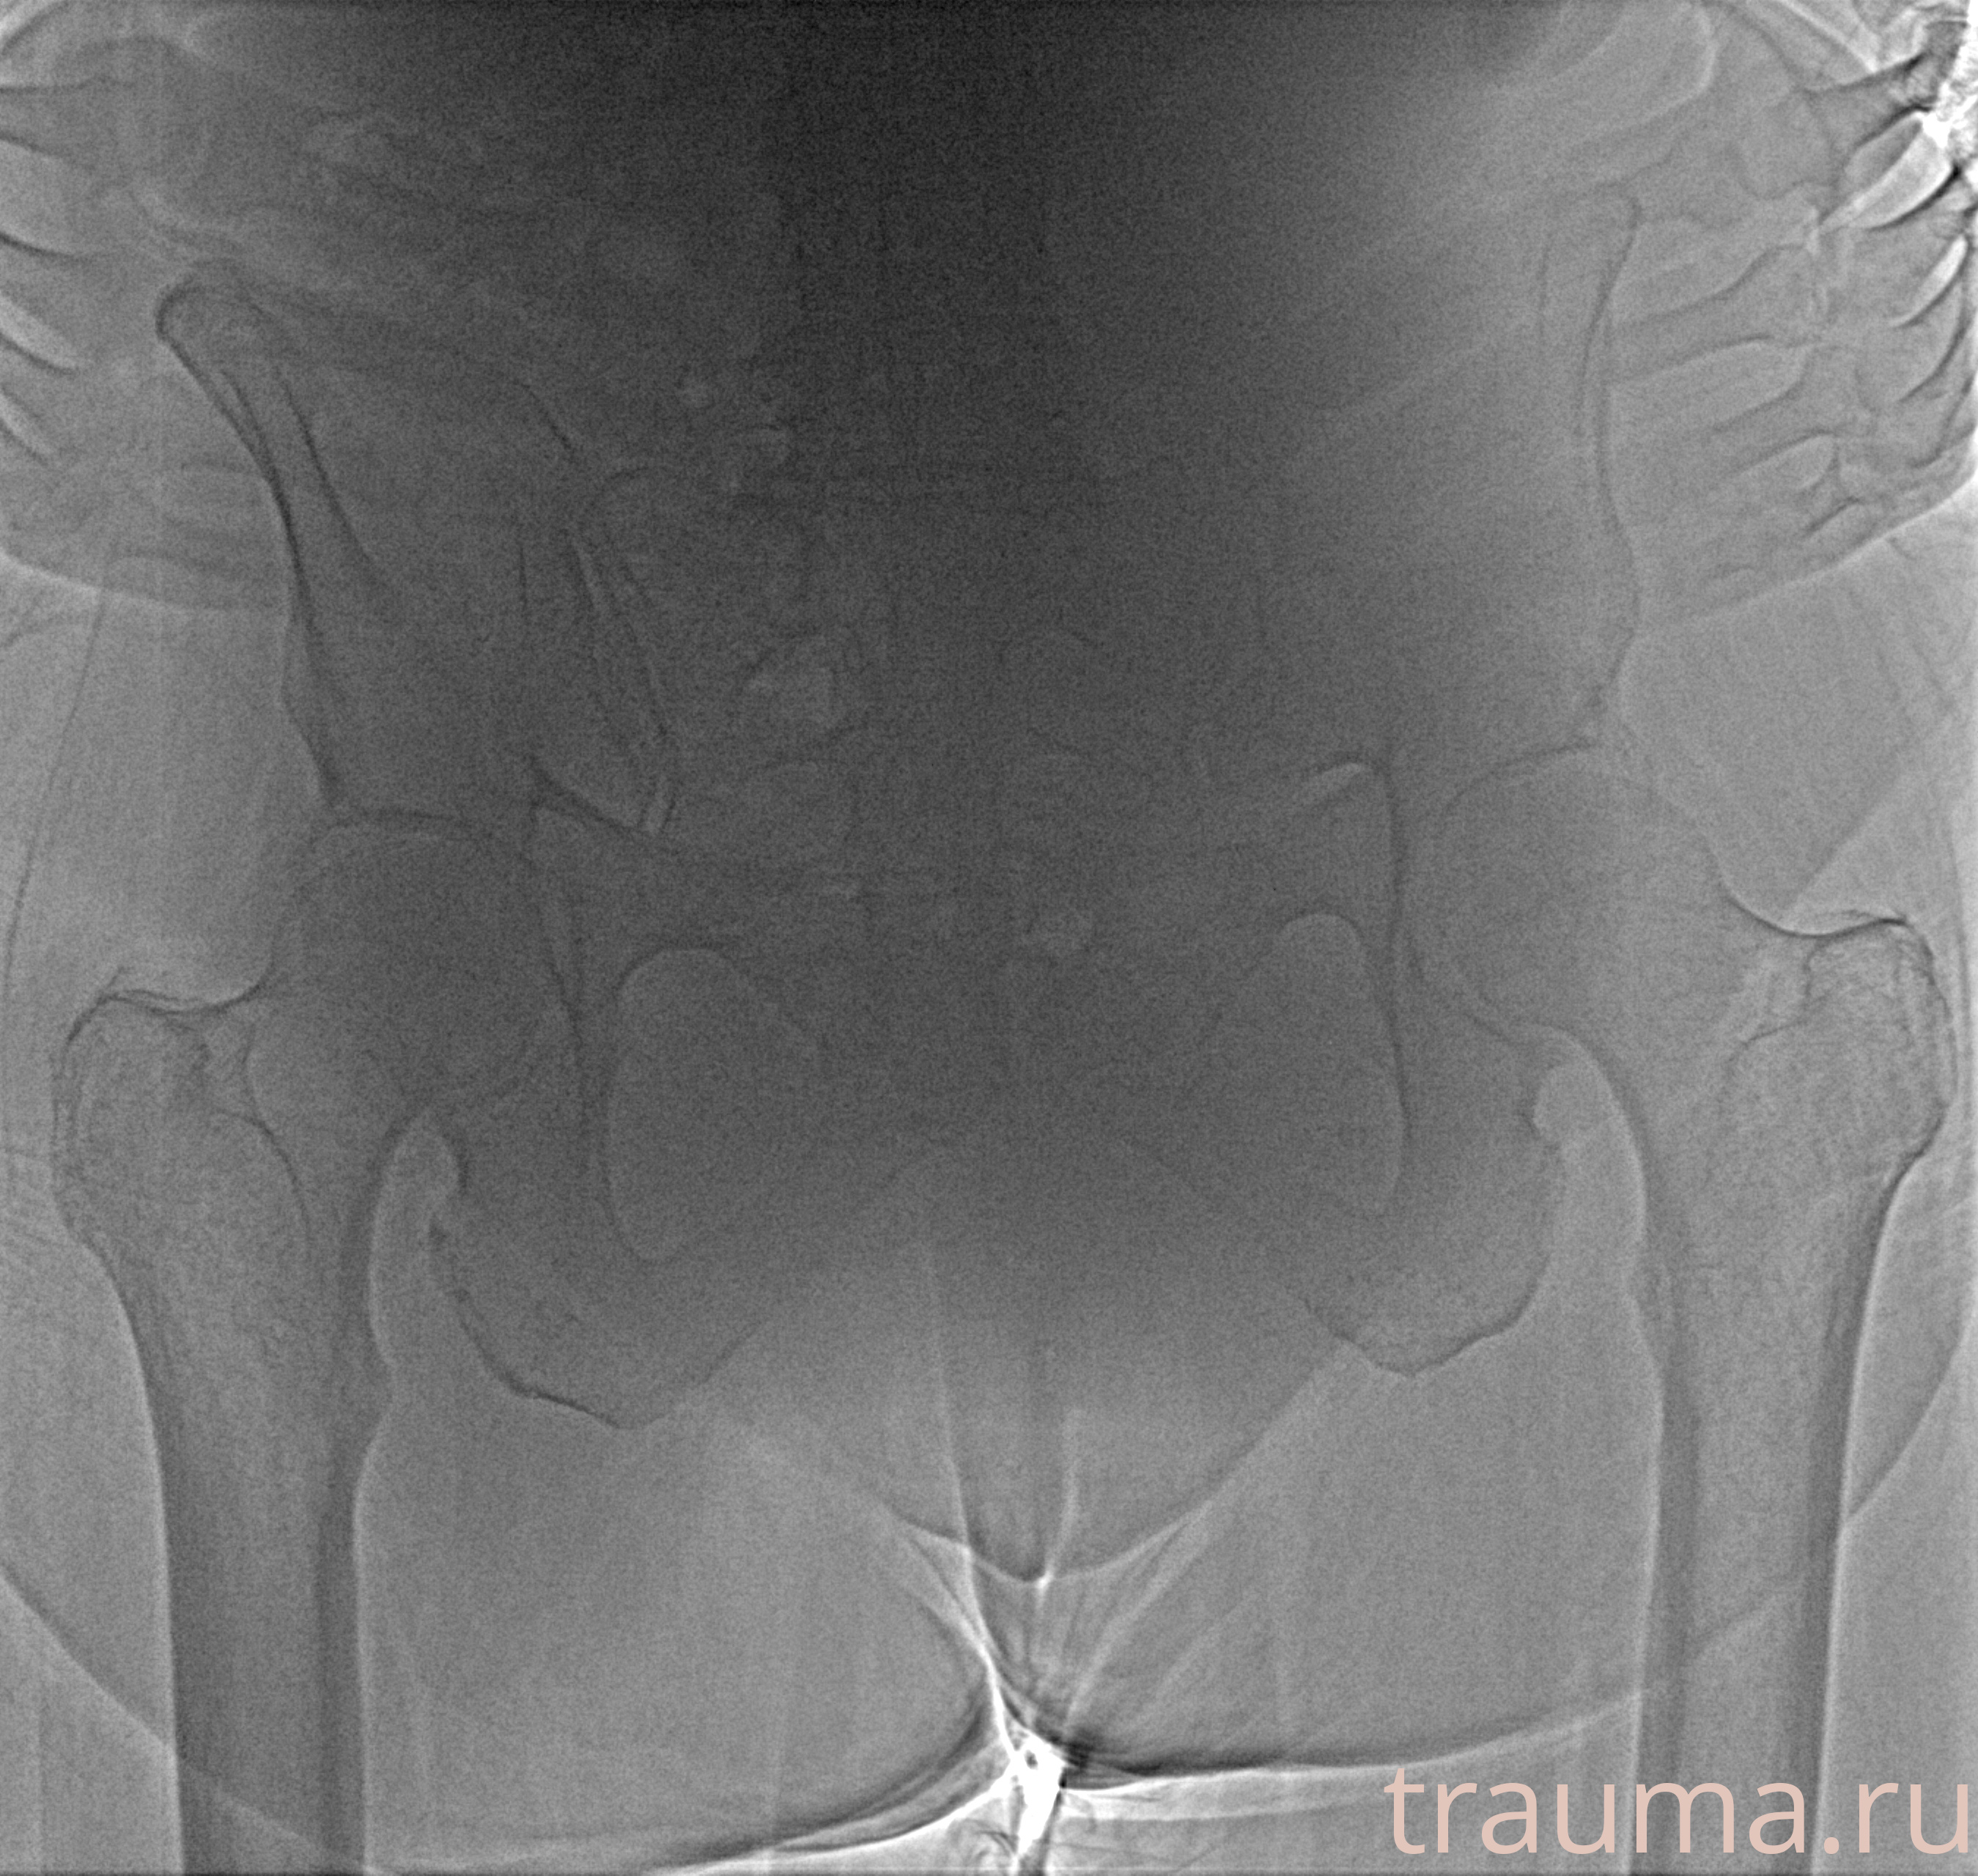

Рентгенограммы

Рентген на дому: по вашему адресу приезжает врач-рентгенолог, травматолог-ортопед с мобильным рентгеновским аппаратом, проводит диагностику травмы или заболевания, делает необходимые рентгенограммы, дает рекомендации по дальнейшему лечению. Получить качественные снимки в домашних условиях возможно благодаря уникальной методике, разработанной МосРентген Центром для института  Склифосовского